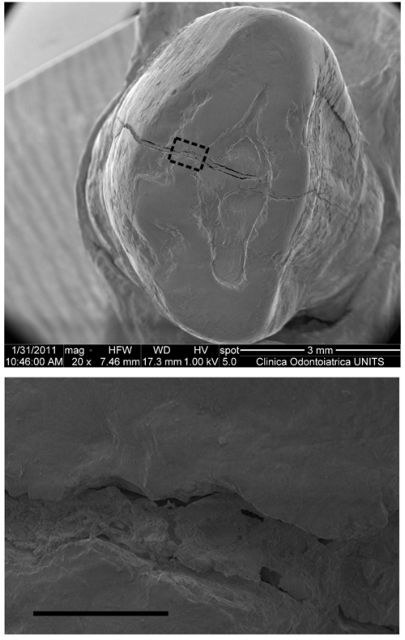

Κατά τη διάρκεια των δοκιμών οι ερευνητές εντόπισαν κάτι περίεργο σε έναν κυνόδοντα. Αποφάσισαν να διερευνήσουν τι υπήρχε στο δόντι μέσω της δημιουργίας μιας τρισδιάστατης εικόνας υψηλής ανάλυσης. Ετσι αποκαλύφθηκε ότι το δόντι είχε σπάσει και η κάθετη ρωγμή που υπήρχε σε αυτό καλύφθηκε με κάποιο υλικό.

Η υπέρυθρη φασματοσκόπηση που έκαναν οι ερευνητές στο δόντι αποκάλυψε ότι το υλικό του σφραγίσματος ήταν κερί μέλισσας. Η περαιτέρω μελέτη της γνάθου έδειξε ότι ανήκε σε έναν άνδρα ηλικίας 24-30 ετών.